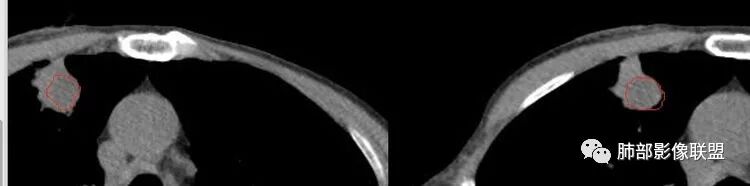

南边:宽基底与胸膜相连桃尖征、U型凹陷、刀切征密度均匀,按理这一部分就是典型的炎性病变的特点

南边:周围晕、细微毛刺都属于炎性特点这一部分单独拿出来类圆形,边缘光滑,按理恶性特征不明显;但是加在一起,转移瘤就不排除总体倾向于炎性,转移瘤不除外

这里毛刺还是粗

转移瘤不能排除

南边:就目前的征象符合炎性,我认为炎性病变一定有但是有部分边缘膨隆,恶性不能排除,等炎性吸收后看看,或穿刺血管纠集南边:

南边:我们担心的,它是在一个转移的基础上,还有合并有炎症,担心这个隐藏在其中,因为它这个边缘,是不是很清楚光滑哈,但是我们都记得转移瘤,他很多都是边界清楚光滑的,对不对。就觉得,中间这个结节跟周围的病灶好像形态、密度各方面都不一致的。我就担心它是一个转移瘤,合并感染,周围炎性病变,中间是一个转移瘤结节这样的就麻烦了。所以常规我会建议他抗炎治疗后复查。看看那个残留的病灶怎么样,本质是如何,要么穿刺,这个病变我只能说炎性它一定有。南边:里面那个病灶就是那个类圆形的病灶,跟外面那个肯定是不一致的,就那个类圆形病灶,到底是一个转移瘤,还是单纯炎性病变的部分。目前这个片只能等复查,毕竟边缘是膨隆的,而且我们刚才也说了,转移瘤的特点,如果血道转移,他就是边界清晰光滑的。所以成这样,有这么巧的话你就没办法。南边:关于血管纠集,它就这样的,炎性病变也可以这样表现,牵拉过来,原理不同,但是影像表现已经表现很类似,我们往往关注支气管。支气管进入这个病灶的表面的时候是否堵塞,或者血管,进入这个病灶里面,是否走行是否自然;这些这些可能价值大一些,但是他是不是一个恶性征象,是;但是它的比例就是在炎性病变也不低。原发呢,不敢说没有,但是一般来说几率偏低吧。